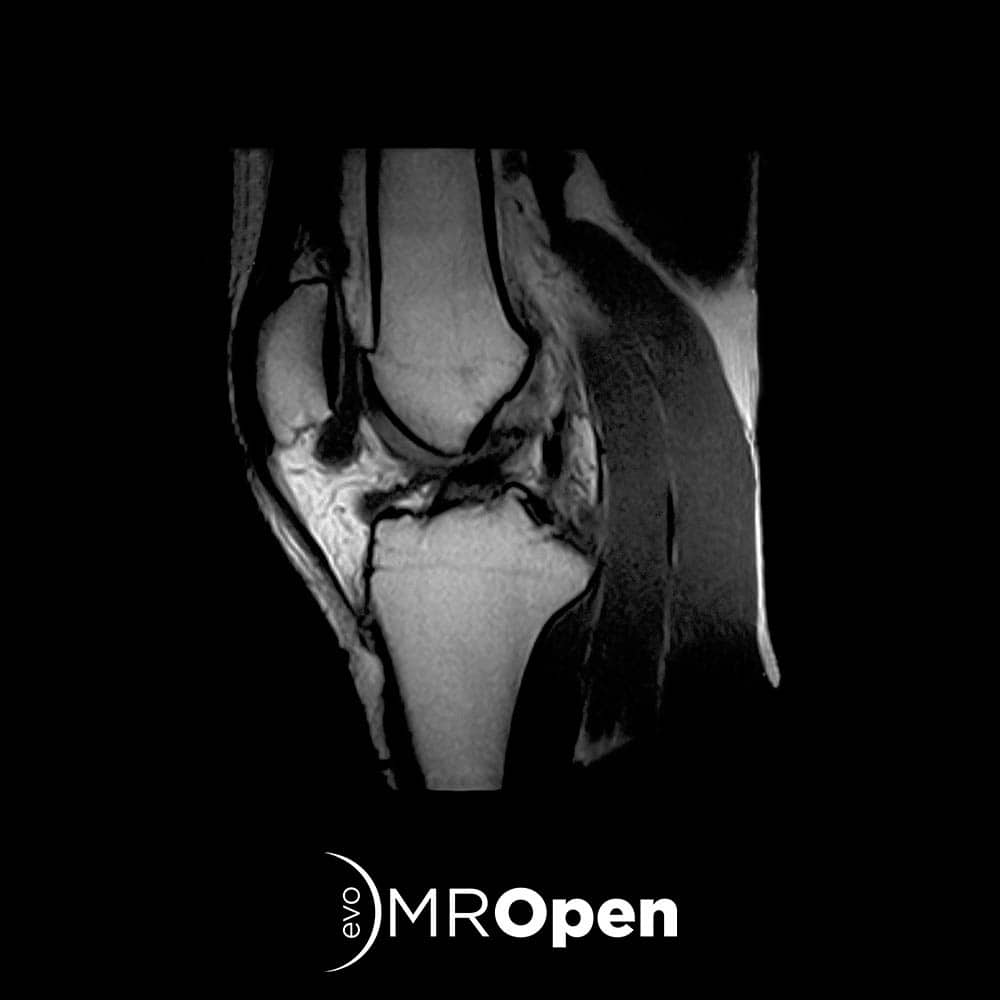

EVERYDAY LIFE

With MROpen Evo you can achieve all the standard MRI procedures for MSK and Neuro imaging. Thanks to a complete set of anatomy-dedicated receiving coils and customized examination protocols setup, your normal daily routine is completely covered, with optimized workflow, high level image quality and unique patient comfort.

To cover specific needs, differentiate your offer and increase the total number of patients MROpen Evo is a perfect choice for your centre as a stand alone scanner or associated with a traditional MRI.